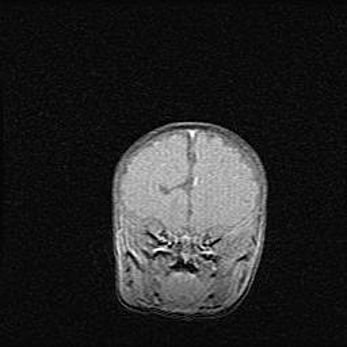

Открытая гидроцефалия.

Возраст: 9 месяцев 12 дней

Вес: 6800 г

Пол: мужской

Окружность головы: 41,5 см

Срок гестации: 28 недель

Гидроцефалия головного мозга у новорожденных имеет характерный признак: опережающий рост окружности головы приводит к визуально хорошо определяемой гидроцефальной форме сильно увеличенного в объёме черепа. Детские неврологи определяют следующие симптомы гидроцефалии у грудничков: выбухающий напряжённый родничок, частое запрокидывание головы, смещение глазных яблок к низу.